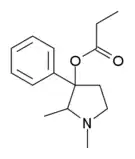

The pharmacodynamic response to an opioid depends upon the receptor to which it binds, its affinity for that receptor, and whether the opioid is an agonist or an antagonist. For example, the supraspinal analgesic properties of the opioid agonist morphine are mediated by activation of the μ1 receptor; respiratory depression and physical dependence by the μ2 receptor; and sedation and spinal analgesia by the κ receptor. Each group of opioid receptors elicits a distinct set of neurological responses, with the receptor subtypes (such as μ1 and μ2 for example) providing even more [measurably] specific responses. Unique to each opioid is its distinct binding affinity to the various classes of opioid receptors (e.g. the μ, κ, and δ opioid receptors are activated at different magnitudes according to the specific receptor binding affinities of the opioid). For example, the opiate alkaloid morphine exhibits high-affinity binding to the μ-opioid receptor, while ketazocine exhibits high affinity to ĸ receptors. It is this combinatorial mechanism that allows for such a wide class of opioids and molecular designs to exist, each with its own unique effect profile. Their individual molecular structure is also responsible for their different duration of action, whereby metabolic breakdown (such as N-dealkylation) is responsible for opioid metabolism.

Several semi-synthetic opioids were developed in Germany in the 1910s. The first, oxymorphone, was synthesized from thebaine, an opioid alkaloid in opium poppies, in 1914.[228] Next, Martin Freund and Edmund Speyer developed oxycodone, also from thebaine, at the University of Frankfurt in 1916.[229] In 1920, hydrocodone was prepared by Carl Mannich and Helene Löwenheim, deriving it from codeine. In 1924, hydromorphone was synthesized by adding hydrogen to morphine. Etorphine was synthesized in 1960, from the oripavine in opium poppy straw. Buprenorphine was discovered in 1972.[228]

The first fully synthetic opioid was meperidine (later demerol), found serendipitously by German chemist Otto Eisleb (or Eislib) at IG Farben in 1932.[228] Meperidine was the first opiate to have a structure unrelated to morphine, but with opiate-like properties.[199] Its analgesic effects were discovered by Otto Schaumann in 1939.[228] Gustav Ehrhart and Max Bockmühl, also at IG Farben, built on the work of Eisleb and Schaumann. They developed "Hoechst 10820" (later methadone) around 1937.[230] In 1959 the Belgian physician Paul Janssen developed fentanyl, a synthetic drug with 30 to 50 times the potency of heroin.[211][231] Nearly 150 synthetic opioids are now known.[228]